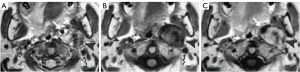

Neurofibroma in the carotid space may be sporadic or a part of neurofibromatosis. Computed tomography (CT) or magnetic resonance imaging (MRI) findings of neurofibromas are often similar to those of schwannomas (Figure 8). Localized lesions typically manifest as masses that grow in a longitudinal and fusiform manner along the affected nerve (5). These masses exhibit tapered ends, indicating the parent nerve entering and exiting the tumor (16,17). A “target sign” appearance has also been described, referring to the central hypointense region of the lesion on a MRI T2-weighted imaging (T2WI) image (18).

Lymphadenopathy is the most common pathology of the carotid space. A variety of primary diseases such as lymphoma, inflammation, and secondary diseases such as metastatic lymphadenopathy may involve lymph nodes, manifesting as masses of the carotid space. Enlarged lymph nodes, especially a solitary node, may mimic a primary tumor on CT and MRI. So, although the majority of lymphadenopathy is caused by metastatic tumors, we still describe them as “primary masses”. The imaging findings of diseased lymph nodes vary with different pathologies. Lymphoma may occur at any age with no gender difference, typically manifesting as painless or growing lymphadenopathy, and may have varying enhancement on CT/MRI imaging with extensive involvement and important neck structures encased yet without narrowing of arterial lumen (28-30). Metastatic lymphadenopathy is more frequently seen in middle-aged and elderly males and usually caused by head/neck squamous cell carcinoma, thyroid cancer, and so on. On CT/MRI imaging, it usually manifests as circular enhancement with central necrosis (squamous cell carcinoma), or obvious enhancement with cystic changes or calcification (thyroid cancer) (31-33). Lymph nodes in the carotid space lie anterior, lateral, and posterior to the jugular vein throughout its course in the neck (34). Therefore, enlarged lymph nodes in the carotid space will not be medial to any vessel in the carotid space (Figure 13), which is different from neurogenic tumors.